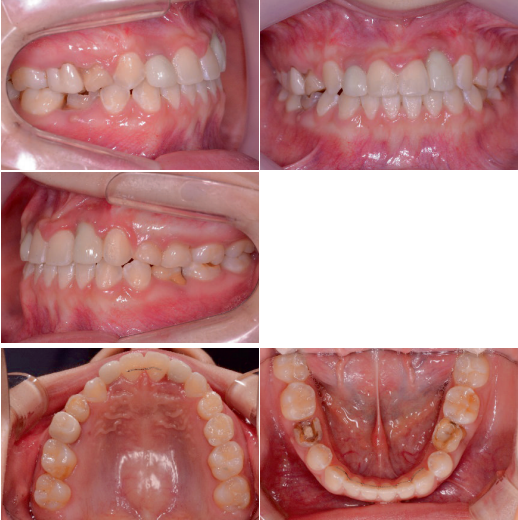

반대교합 수정과 측절치 임플란트 식립및 temporary crown을 이용한 보철수복이 이루어졌습니다. 양측 견치의 수직적 차이가 조금 더 명확해졌습니다.

Occlusal canting을 수정하기 위해 상악 좌측 임플란트보철물에 bracket을 기울여 붙여서 slot의 방향대로 archwire가 삽입되었을때 좌측 견치는 정출되고 우측 견치는 함입되도록 하였습니다.

Slot의 방향에 맞춰 전치부 occlusalcanting이 개선되었습니다. 좌측견치의 정출이확연히 눈에 띕니다.

교정 마무리후 임플란트 상부 보철은 임시보철에서 최종보철로 변경해 주었습니다.

초진시부터 마무리까지 양측 견치 tip을 연결한 선을 기준으로 frontal occlusalplane의 변화를 비교 시occlusal canting의 개선을 확인할 수 있습니다.

부분교정에서 임플란트 조기식립과 상부 보철제작은 occlusal canting과 같은 수직적문제 외에도 scissorbite와 같은 횡적 문제 개선에 유용한 solution이 되므로 임상에서적극적으로 고려할 만합니다.